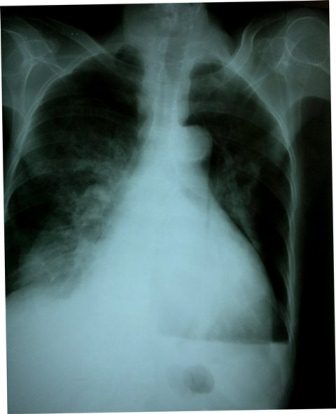

Tràn khí màng phổi